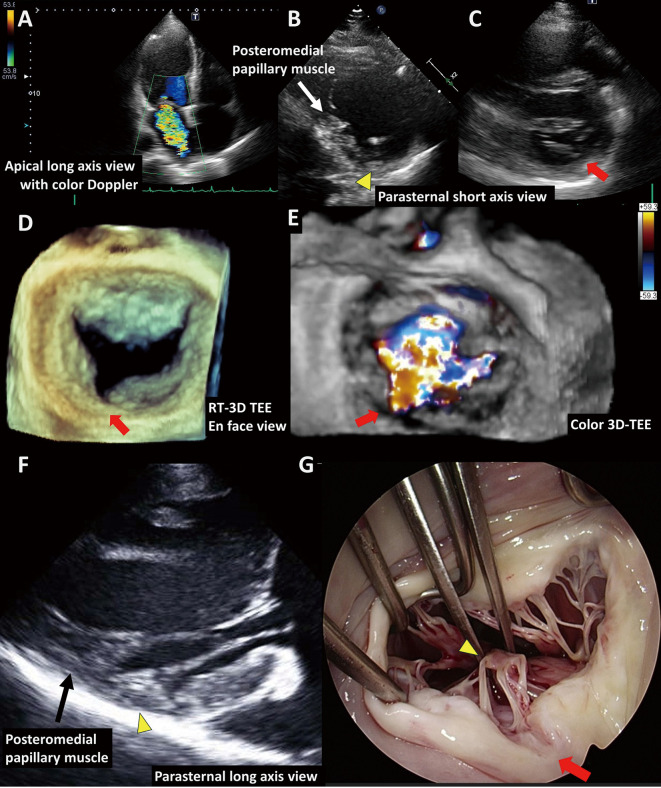

Isolated Cleft of the Posterior Mitral Valve Leaflet With Papillary Muscle Abnormalities.